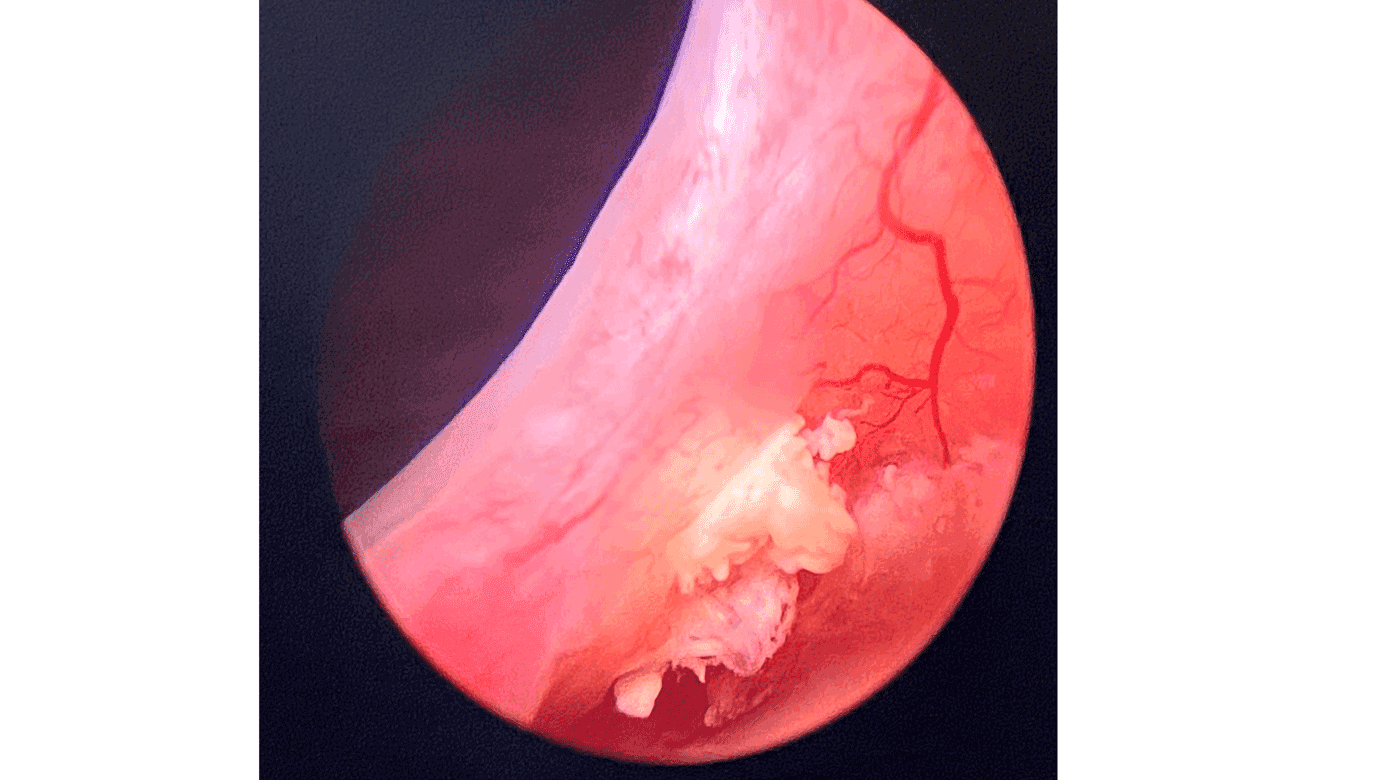

I 2022 blev kvinden henvist til urologisk afdeling på universitetshospital obs ureteritis med kronisk smertetilstand. Der var debut af smertetilstand efter resektion i 2021. Kvinden oplevede igen stressinkontinens som før bulkingoperation. Ved cystoskopi blev der fundet rester af bulkingmateriale ved blærehalsen (Figur 1 C). Kvinden blev over de næste måneder forsøgt behandlet for kroniske smerter, herunder cystoskopivejledt injektion af lidocain, methylprednisolon og hyaluronidase samt aflastende topkateter. Den kroniske smertetilstand forblev uforandret.